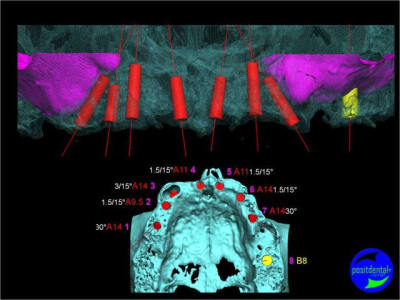

Projet implantaire:

Extraction, pose d’implants Ankylos, pose des piliers Standard définitifs, mise en charge immédiate bi-maxillaire en une chirurgie.

Maxillaire supérieur – extraction 13, 26, 7 implants en MCI, 1 implant en MCR pose summeurs, densification par ostéotme, comblement osseux, bridge provisoire sans fausse gencive avec renfort métallique.

Maxillaire inferieur – extraction 35, 34, 44, 45, 6 implants MCI, comblement osseux, bridge provisoire sans fausse gencive avec renfort métallique.

3D

en attendant la pano voici les coupes de la S.I.A.O.